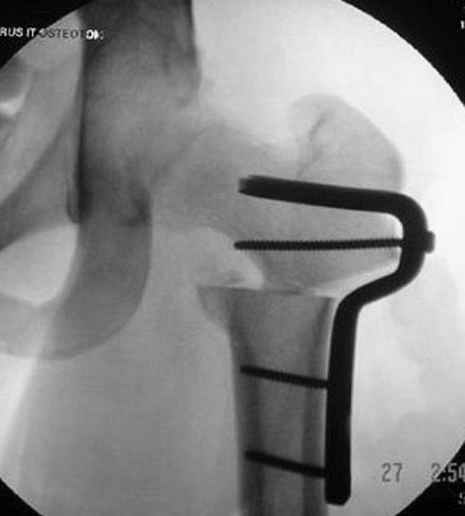

5:24 Рентгенограмма таза, вызывают врача ортопеда (снимок N1), его диагноз: закрытый переломо-вывих правого тазабедренного сустава, получает добро на закрытую репозицию в приемном отделении

N 2

6:20 ответстенный врач принимает решение о репозиции в условиях операционной, предупреждаются родственники и больной, что при неудачной закрытой репозиции, о возможности открытой репозиции и фиксации задней стенки вертлужной впадины.

7:30 начало операции, больной на спине, попытка репозиции после анестезии N3, укладка больного на боку, доступ Kocher- Langenbeck, состояние седалищнего нерва около 2.5см кровоподтек, через joistick головка бедра приподнята, освобовождение сустава, фрагмент заднего края более 3х4 см репонирован на свое место. После промывания

сустава, репозиция вывиха (N4), фиксация фрагмента 2.7(4) мм шурупами и допольнительно реконструктивной пластиной на 8 дырок, фиксация 3.5мм шурупами проксимально и дистально.

Интраоперционные N5 косая запирательная и N6 подвздошный снимок